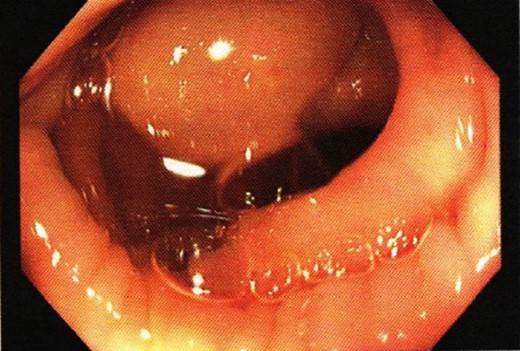

A 43-year-old man presented with seven months of intermittent lower abdominal pain and altered bowel habit. The patient denied having similar symptoms in the past or any history of abdominal surgery. He had no past medical history or familial history of colorectal malignancy. On presentation, he appears well with no tenderness or palpable masses on abdominal examination. A computed tomography of the abdomen and pelvis demonstrated a 13 × 10 × 10 mm3 ovoid lesion in the distal descending colon and no evidence obstruction and associated regional lymphadenopathy (Fig. 1). A colonoscopy performed confirmed the ovoid mass, for which an inverted diverticulum was initially suspected (Fig. 2). Mucosal biopsies did not demonstrate any pathological changes. The patient underwent laparoscopic high anterior resection with an uncomplicated post-operative course and a rapid recovery.

Colonoscopic finding showing a smooth distal descending colon tumour.